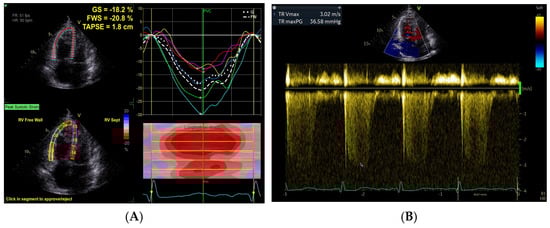

Prognostic Value of the RVFWLS/PASP Ratio in Pulmonary Arterial Hypertension

Background: The right ventricular free wall longitudinal strain to pulmonary arterial systolic pressure (RVFWLS/PASP) ratio is an emerging echocardiographic index for evaluating right ventricular–pulmonary artery (RV-PA) coupling. This study aimed to evaluate its prognostic significance and incremental value in risk stratification for patients [...] Read more.

Background: The right ventricular free wall longitudinal strain to pulmonary arterial systolic pressure (RVFWLS/PASP) ratio is an emerging echocardiographic index for evaluating right ventricular–pulmonary artery (RV-PA) coupling. This study aimed to evaluate its prognostic significance and incremental value in risk stratification for patients with pulmonary arterial hypertension (PAH). Methods: We conducted a retrospective–prospective cohort study of 149 adult PAH patients (87 idiopathic PAH and 62 connective tissue disease-associated PAH). RVFWLS was measured via speckle tracking echocardiography, and PASP was estimated using Doppler. The primary endpoint was event-free survival, defined as the first occurrence of all-cause mortality, lung transplantation, or rehospitalization for right heart failure. Kaplan–Meier and multivariate Cox regression analyses were performed to identify independent predictors. Results: During a median follow-up of 32 months, 78 primary events occurred. Patients in the lower RVFWLS/PASP group (<0.246%/mmHg) exhibited significantly worse exercise capacity, higher NT-proBNP levels, and poorer hemodynamics compared with the higher group (≥0.246%/mmHg) (all p < 0.001). The event-free survival rate for the composite endpoint was significantly lower in the group with reduced RVFWLS/PASP compared with that observed in the higher RVFWLS/PASP group (log-rank p < 0.05). Multivariate Cox regression analysis demonstrated RVFWLS/PASP ≥ 0.246%/mmHg was independently predictive of reduced risk for the primary endpoint (HR = 0.46, 95%CI 0.23–0.93, p < 0.05). Moreover, RVFWLS/PASP facilitated additional risk stratification among patients classified as low risk based on established models (FPHN, COMPERA 2.0, and REVEAL Lite 2). Conclusions: RVFWLS/PASP is a robust, independent determinant of long-term prognosis in patients with PAH. As a noninvasive measure of RV-PA coupling, it provides significant incremental value for clinical risk assessment and treatment monitoring. Full article